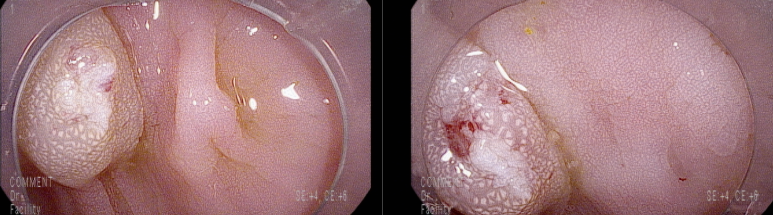

제자리 암종 소견 보였던 진행성 용종의 국소 제발이 없음을 확인2020년 8월 18일1분 분량http://blog.naver.com/ejercicio/220899223880 상기 환자 추적 대장 내시경상 경을 동반했던 병변의 저부는 흉터 조직 변화가 있어 주변에 점막 요철이 있으나 정상 점막 표면을 보여준다. 완전 절제임을 확인이외 다른 병변 발견되어 용종 절제술약간 남아서 조직겸자로 제거동대문구 답십리 우리안애, 우리안愛 내과, 건강검진 클리닉 내과 전문의 전병연#동대문구 #성동구 #답십리역 #장안평역 #용답역 #청량리역 #신답역 #한양대역 #왕십리역 #답십리사거리 #촬영소사거리 #전농동사거리 #내과 #국가검진 #위내시경 #대장내시경 #갑상선초음파 #복부초음파 #경동맥초음파 #심장초음파 #암검진 #래미안위브아파트 #엘림스퀘어 #두산아파트 #동아아파트 #한양아파트 #동답한신아파트 #두산위브아파트 #힐스테이트청계아파트 #래미안미드카운티 #청솔우성